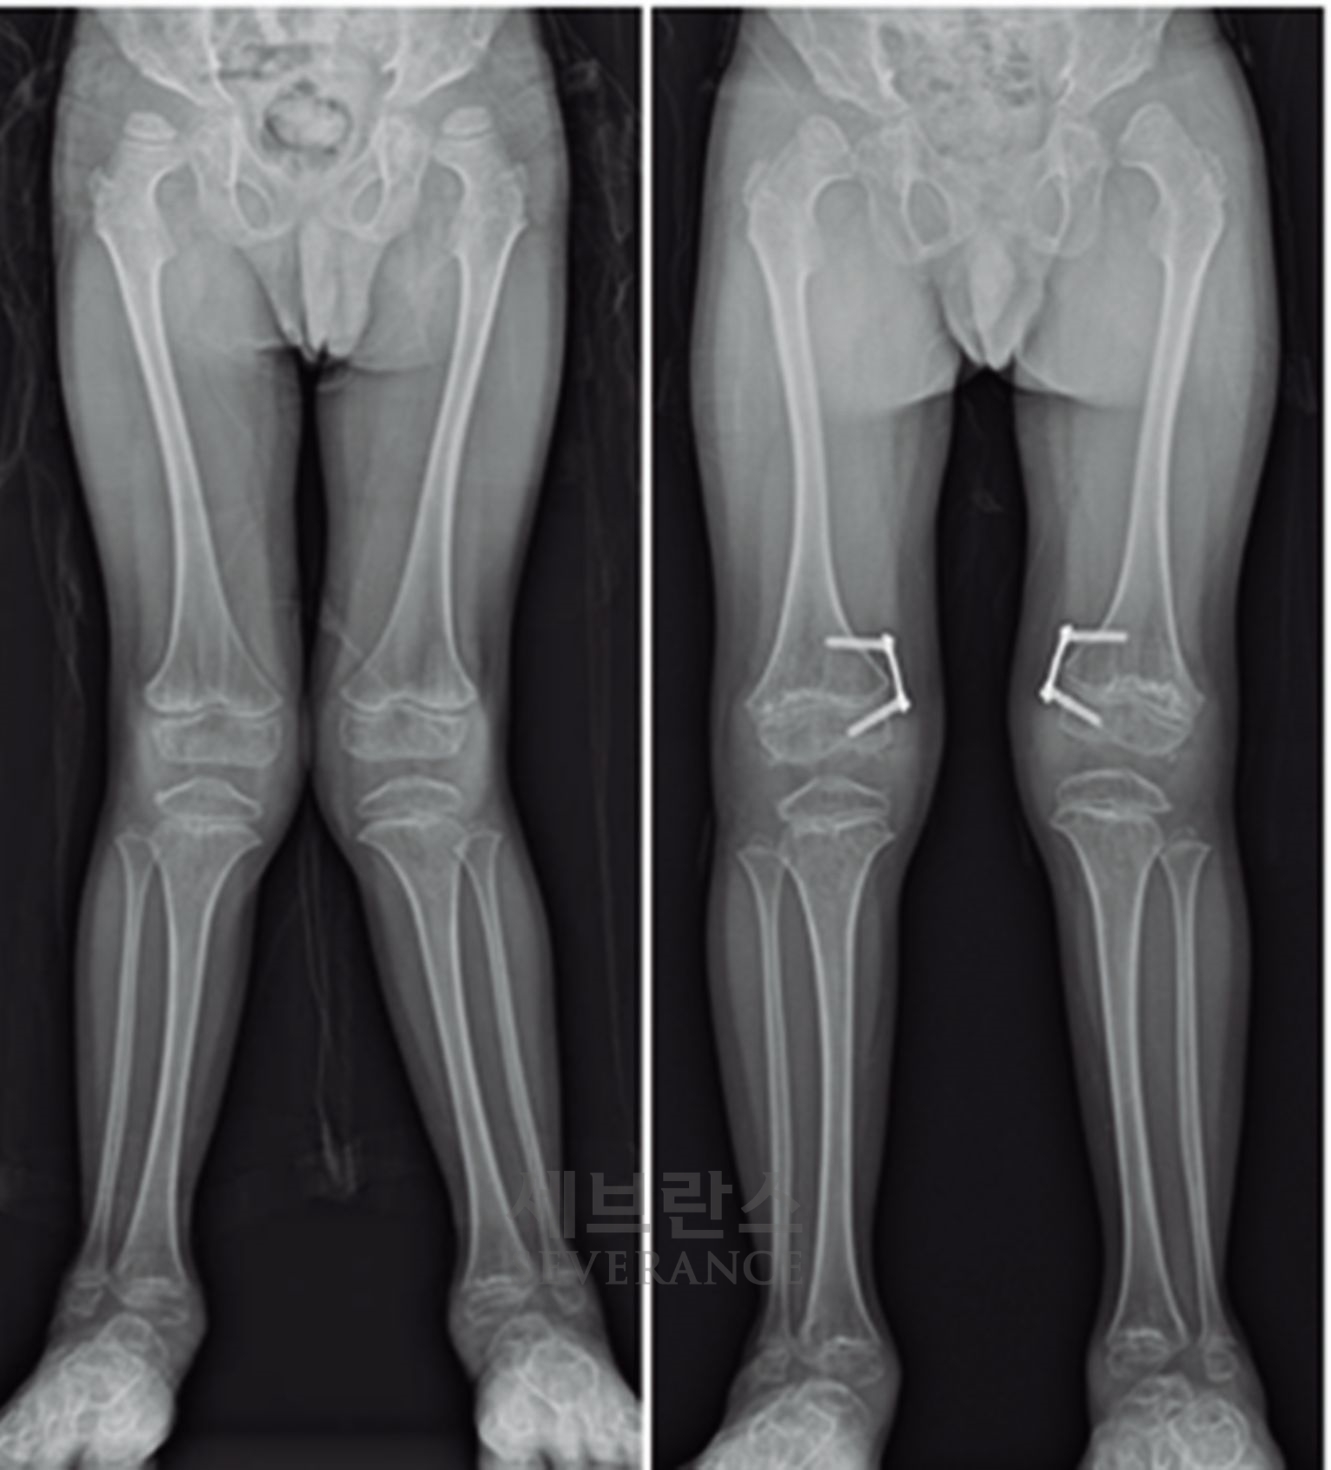

구루병으로 발생한병적 내반슬(O다리) 변형에 대해

절골 교정술을 시행한 환아